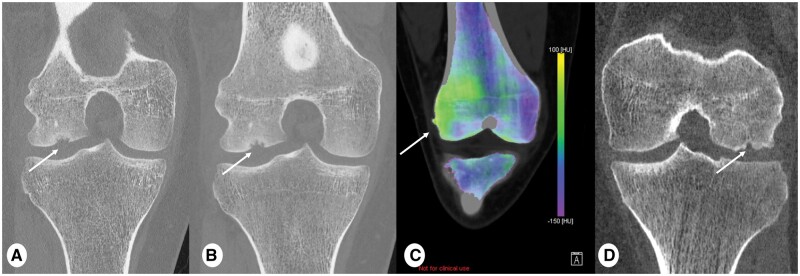

Recent advancements in CT technology have introduced a revolutionary innovation to practice known as the Photon-Counting detector (PCD) CT imaging. The pivotal hardware enhancement of the PCD-CT scanner lies in its detectors, which consist of smaller pixels than standard detectors and allow direct conversion of individual X-rays to electrical signals. As a result, CT images are reconstructed at higher spatial resolution (as low as 0.2 mm) and reduced overall noise, at no expense of an increased radiation dose. These features are crucial for paediatric imaging, especially for infants and young children, where anatomical structures are notably smaller than in adults and in whom keeping dose as low as possible is especially relevant. Since January 2022, our hospital has had the opportunity to work with PCD-CT technology for paediatric imaging. This pictorial review will showcase clinical examples of PCD-CT imaging in children. The aim of this pictorial review is to outline the potential paediatric applications of PCD-CT across different anatomical regions, as well as to discuss the benefits in utilizing PCD-CT in comparison to conventional standard energy integrating detector CT.